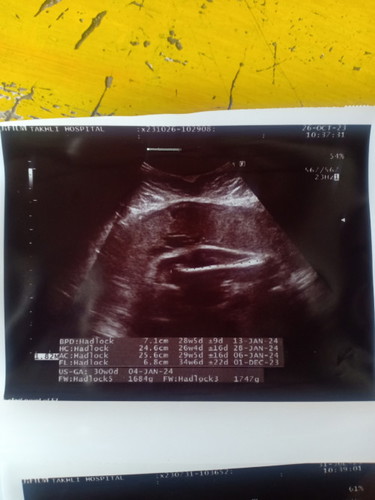

ดูน้ำหนักน้องตรงไหนเหรอคะ

1684g ข้างล่างเลยค่ะ

บรรทัดล้างสุดคะ

ล่าสุดคะ 1684 g.